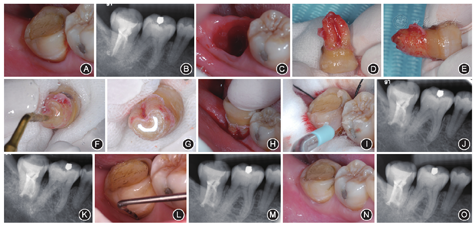

患者女性,47岁,2010年6月因右下后牙慢性牙髓炎在南方医科大学口腔医院行根管治疗,病历记录患牙为C型根管,近中根管中下段钙化不通。治疗后无不适。2014年6月因患牙无诱因出现咀嚼疼痛就诊。否认咬硬物史。否认全身系统性病史,否认药物过敏史。检查可见47

面大面积树脂充填物,边缘色素沉着,未探及继发龋坏及明显隐裂纹,叩痛(+),无松动,牙龈未见明显异常,牙周探诊深度2~3 mm(图1A)。根尖X线片示47髓室及根管内致密充填物,近中根管中下段欠填伴根管影像消失,远中根管少许超填伴根尖周低密度影(图1B)。诊断:47慢性根尖周炎。考虑患牙根尖周炎症持续存在可能的原因:C型根管存在根管钙化,初次根管治疗不彻底,根管内残存的微生物引起慢性根尖周炎持续存在;根管充填物超填,引起根尖周异物反应。由于患牙为C型根管,解剖结构复杂,近中根管中下段钙化并伴远中根管充填物超填,根尖炎症持续存在,根管再治疗远期成功率极低。此外,患牙所处牙列解剖位置靠后,咬肌肥厚,邻近下牙槽神经管,颊侧骨皮质外斜线加强,显微根尖外科手术视野不佳,创伤较大,风险高。同时,患者保留患牙的意愿强烈。在告知患者手术风险并获得其知情同意后,最终选择行意向性牙再植术。

手术由2名操作者完成,术者一在局麻下微创完整拔除患牙交给术者二,拔牙窝待植(图1C)。术者二用生理盐水纱布包裹离体牙冠,检查见根尖部有炎性肉芽组织,远中根尖孔可见牙胶(图1D,图1E)。在生理盐水喷射降温下用高速金刚砂车针切除病变根尖3 mm,检查患牙根部无裂纹,牙根断面可见C型根管,近中根管钙化。切除病变根尖,用超声(BL,韩国)行倒预备,去除3 mm牙胶及钙化物(图1F)。用超声(奥丹,丹麦)去除根面上附着的牙石及下方可疑的炎性肉芽组织。生理盐水冲洗,三用枪轻吹干燥根尖,iRoot BP Plus(Innovative Bioceramix,加拿大)行根尖倒充填(图1G)。将患牙重新植入牙槽窝内,咬合就位(图1H)。47离体操作时间短于10 min。颊舌侧牙龈对位缝合,用Super-BondC&B(Sun Medical,日本)固定患牙和邻牙(图1I)。术后即刻根尖X线片示47基本复位,牙周膜间隙较术前增宽,根尖部根管内可见致密充填物相连成C形,46、47牙冠间约1 mm间隙(图1J)。1周后复诊拆线,患牙咀嚼疼痛症状已消失,叩痛(±),松动Ⅰ度。1个月后复诊,患牙无咀嚼不适,叩痛(-),无松动。根尖X线片示47根尖骨质密度较术前稍增加(图1K),术后半年复诊,患牙无不适,临床各项检查均恢复正常。根尖X线片示47根尖部低密度影消失,骨质密度恢复正常,46、47牙冠之间的间隙缩小(图1L,图1M)。术后1年、2年半复诊,患牙无不适,无食物嵌塞,46、47根尖无明显异常,牙冠接触点恢复正常(图1N,图1O)。